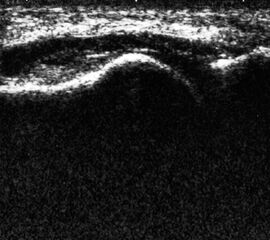

Ganglien an Sprunggelenk und Fuß

Ganglien imponieren als runde, echofreie Raumforderungen.

Abbildung 9

Lagerung: Rückenlage.

Schnittebene: LS und TS über der Pathologie.

Referenzstrukturen: Reproduzierbare knöcherne Landmarken in Abhängigkeit von der Lokalisation. Befunde: Ganglien finden sich häufig im fibularen Anteil der Gelenkkapsel des oberen Sprunggelenks (Abb. 9), aber auch an den Gelenkspalten und paratendinös im Bereich von Sehnenscheiden streck- oder beugeseitig. Ganglien sind sonographisch als meist runde echofreie Raumforderungen gelenk- oder sehnennah darstellbar.